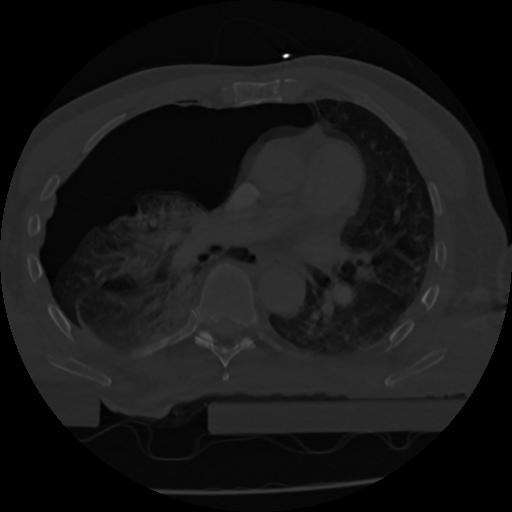

22 ANGIO,CE,Vol,0.5,ANGIO,,